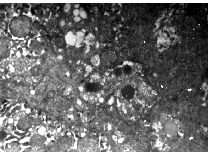

Непосредственными ультраструктурными проявлениями нарушения желчеобразования и желчевыделения являются изменения билиарных полюсов гепатоцитов, на которых выявлена деструкция микроворсинок, желчные капилляры расширены и заполнены мицеллами желчи (рис. 4). Обращает на себя внимание аномальное распределение мицелл желчи по цитоплазме гепатоцитов, которое характеризовалось их скоплением на апикальных полюсах. Этот факт подтверждает предположение о возможном активном транспорте желчи через апикальный полюс в условиях внутриклеточного холестаза [14]. Биохимический анализ крови показал наличие на фоне указанных изменений синдрома холестаза, кото-рый сопровождался повышением уровня как прямого (7,3 1,5), так непрямого билирубина (20,3 2,3).